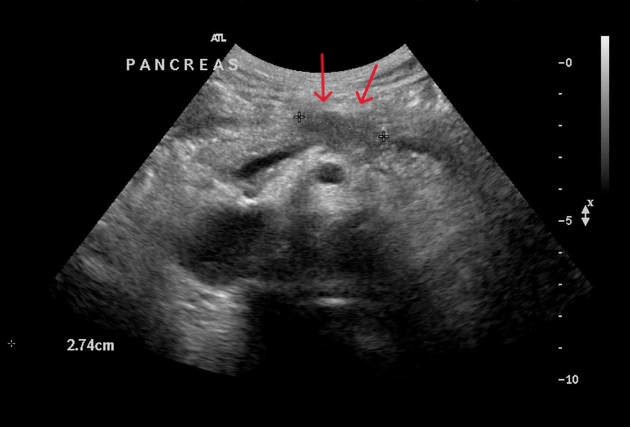

5. és 6. kép:

Hasnyálmirigy daganat

Ezeken a képeken 2 hasnyálmirigy daganatos esetet láthatunk.

Az 5. képen a testben helyezkedik el egy echoszegény terület ami jelzi a daganatot (piros nyilak). A 6. képen a hasnyálmirigy fejben látható egy körülírtabb terület ami a daganatnak felel meg.